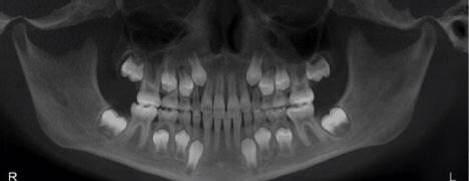

出生时:20颗乳牙的牙冠几乎全部形成并钙化,16颗恒牙牙胚形成恒牙

所以,不光恒牙需要做窝沟封闭,乳磨牙也应该利用它来预防龋齿.